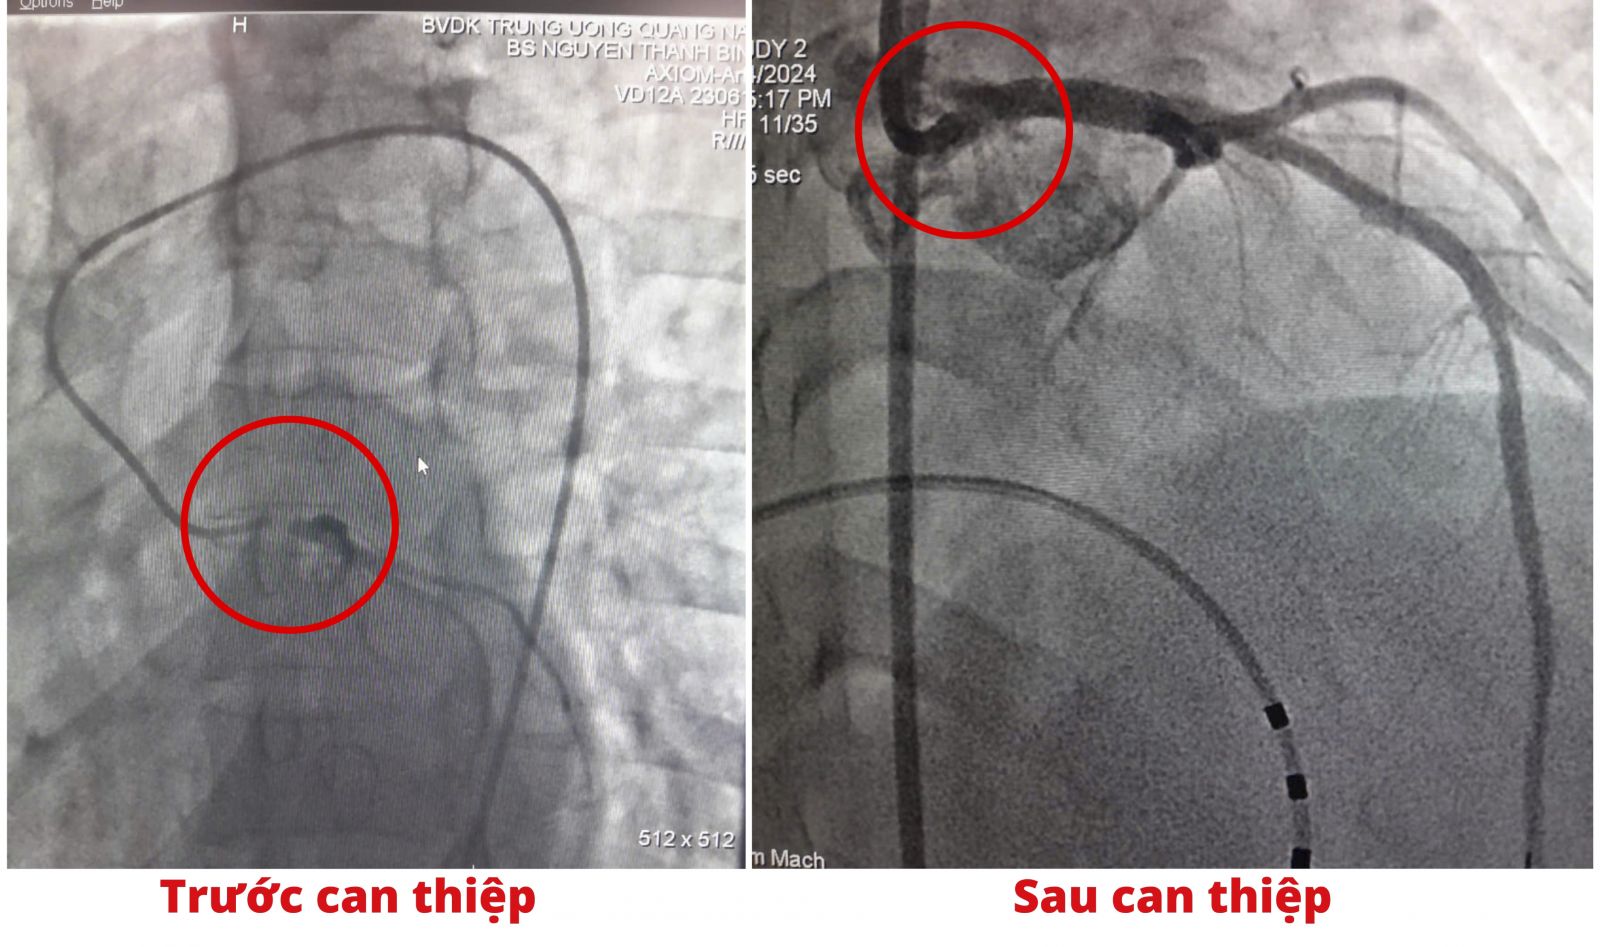

Hình ảnh DSA bệnh nhân tắc thân chung động mạch vành trái và sau can thiệp đã tái thông mạch vành trái.

Khi được chuẩn bị kỹ lưỡng, ekip can thiệp thực hiện thủ thuật nong bóng và đặt 1 stent thân chung động mạch vành trái, thủ thuật can thiệp được thực hiện trong vòng 30 phút. Hình chụp động mạch vành kiểm tra sau can thiệp cho thấy stent thân chung động mạch vành trái đúng vị trí, stent giãn nở tốt, dòng chảy qua thân đạt mức TIMI 3 (tốt nhất). Trong và sau thủ thuật không ghi nhận tai biến.